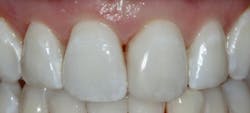

Results

I have found that most posterior teeth can be restored using a single shade. In cases where the tooth structure is very discolored, coupled with a shallow tooth preparation, I opt for an opaque layer beneath my core shade. For anterior cases, the enamel shades offer enough translucency to give the restoration a lifelike appearance. I tend to opt for a core shade to restore chipped incisal edges, and the results have been terrific. Nothing’s worse than a patient coming back with an anterior composite restoration that didn’t hold up; it leads to patients losing confidence in your skills, sometimes negative reviews, wasted chair time, and lost profitability. Polishing this composite is very efficient and effective, and so far, it’s maintained its shine. From my assistants’ perspectives, simplifying my systems made it easier to learn, maintain inventory, and prepare for direct restorations. From my perspective, simplifying composite restorations allows me to reduce chair time, minimize waste, and predictably and efficiently place restorations that my patients love.

Fabricating composite restorations with a simplified system can yield exceptional clinical outcomes and enhance practice profitability.